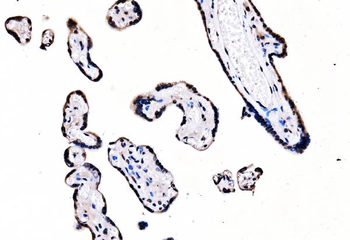

50 μl, 100 μl - MARK3 Recombinant Rabbit Monoclonal Antibody [orb704310]Featured

ICC, IF, IHC-Fr, IHC-P

Human, Mouse

Rat

Rabbit

Recombinant

Unconjugated

50 μl, 100 μl - Featured